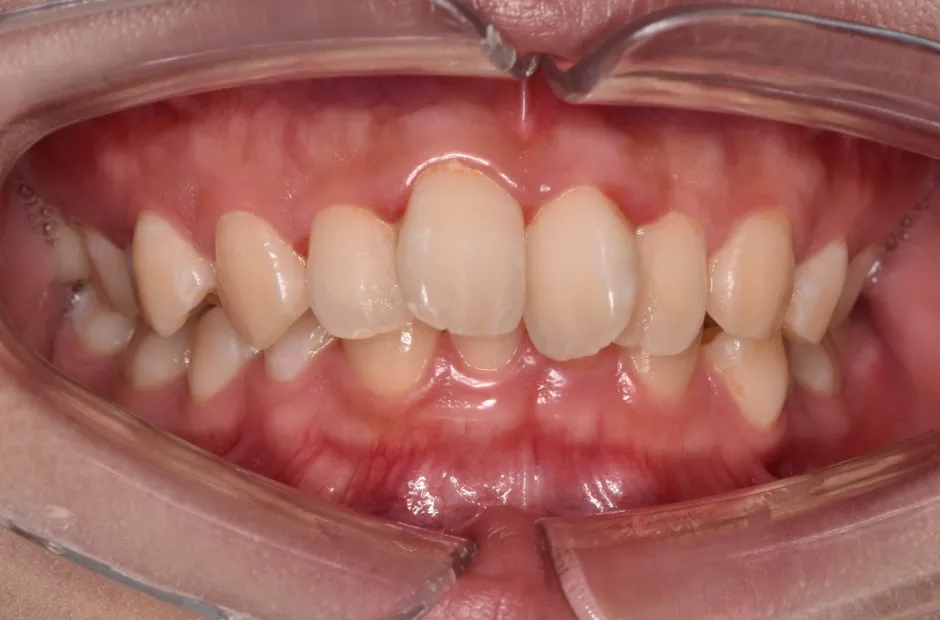

過剰歯

治療後